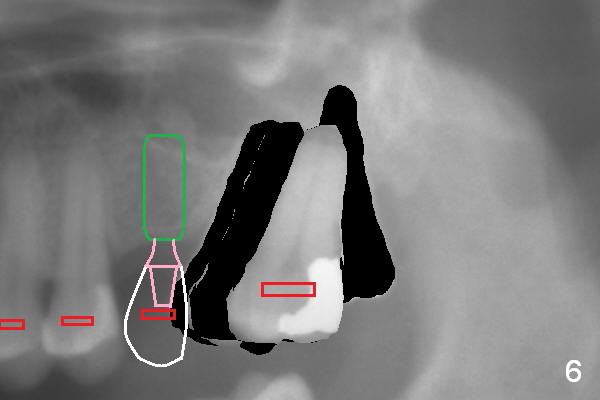

When the tooth #15 is distalized (Fig.3), place an implant at #14 (Fig.4 green), parallel to the tooth #13 and extract #16 (black). When the implant osteointegrates, place an abutment (Fig.5 pink), provisional (white) and bracket at #14. The implant is used as an anchorage to further distalize #15 until the latter reaches the normal position (Fig.6). CT study shows how much the tooth movement is needed prior to implantation.